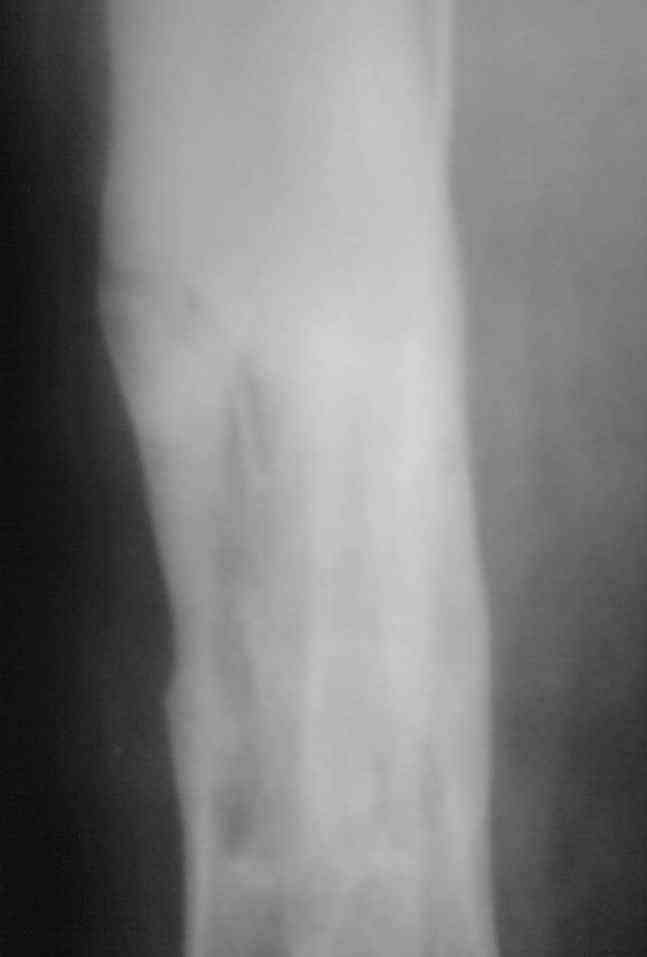

Re: Остеомиелит.

Выкладываю снимки в хронологическом порядке. Снмки все какие есть у больного.